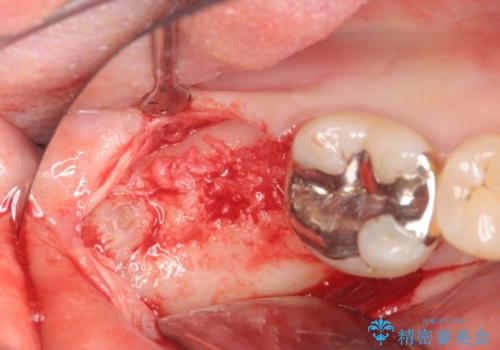

抜歯を余儀なくされる状況ですが、将来的にインプラントによる咬合機能回復を希望されたので抜歯と同時に骨補填剤を填入し骨の造成をしたのちのインプラント治療を計画します。

歯を失い、将来的にインプラントを埋入し咬合機能を回復していく場合、十分な骨量の確保は重要です。

今回抜歯後、骨が十分に確保できないとの判断から抜歯と同時に骨補填剤の填入を行いました。